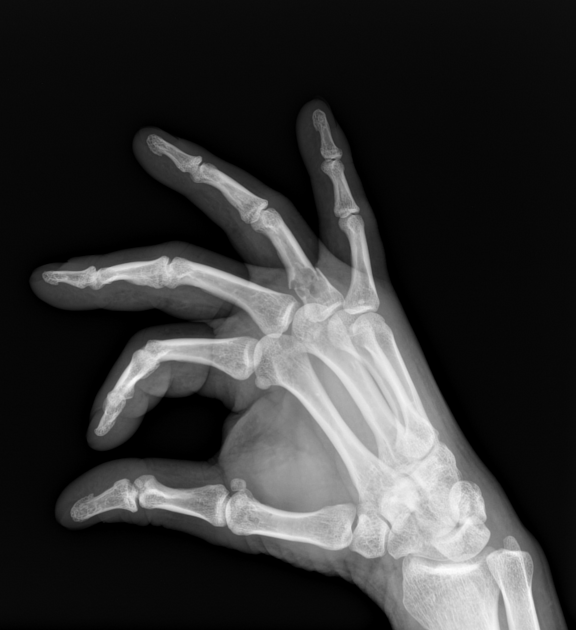

Enchondroma Hand

Enchondroma - Azouz Hand SurgeryAzouz Hand Surgery Enchondromas - Pathology - Orthobullets LearningRadiology- Enchondroma Enchondroma-of-hand LearningRadiology- Enchondroma Enchondroma Hand